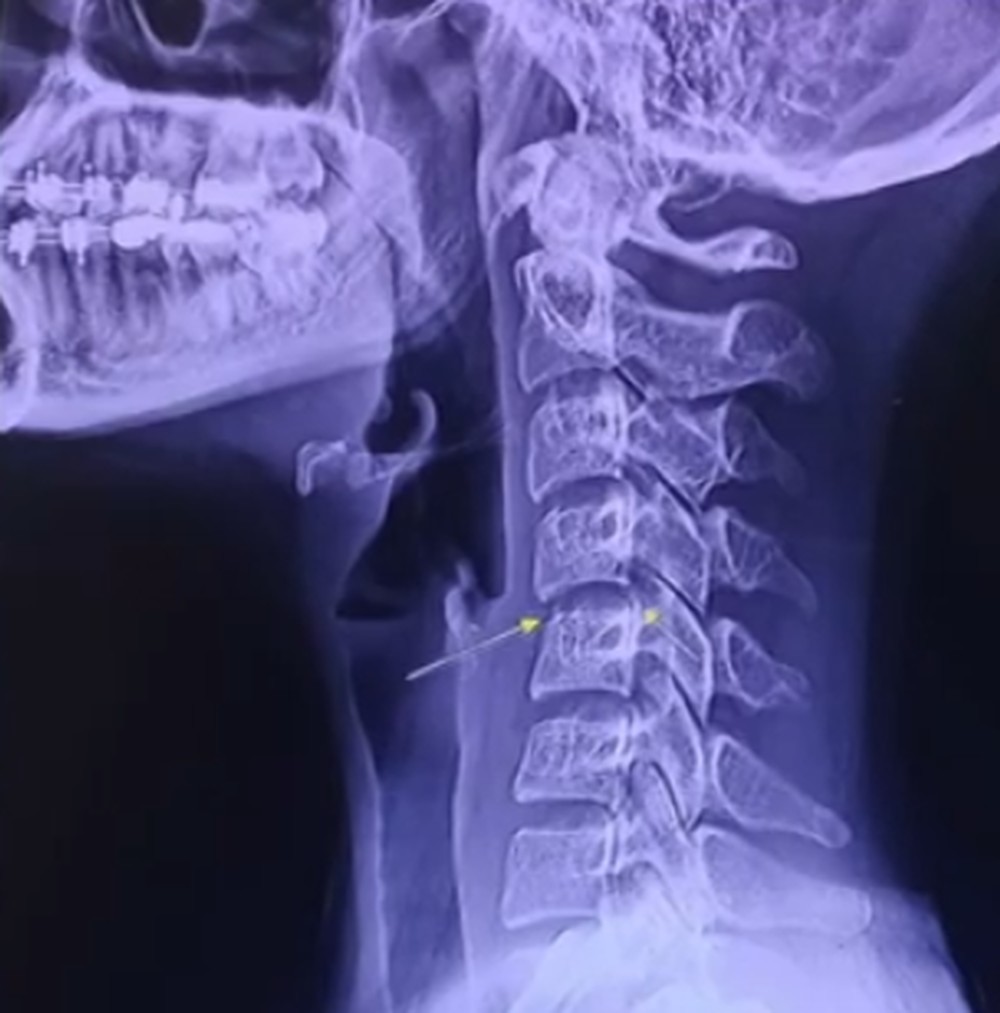

Após passar por exames, foi constata que uma vertebra na altura do pescoço estava fora do lugar. Além disso, Chayada apresentava um quadro de mielite transversa, uma doença que consiste na inflamação da medula espinhal, bloqueando a transmissão de impulsos nervosos. Segundo imprensa local, as massagens praticadas na cantora tinham movimentos de “torcer o pescoço”.

Foto: Reprodução YouTube